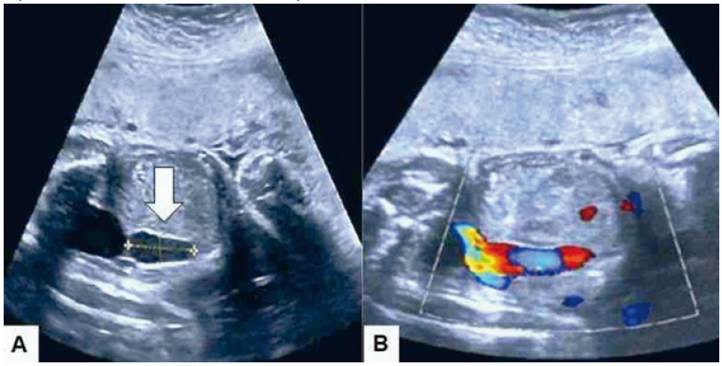

En la ecografía se observó feto femenino de 29 semanas de gestación por mediciones ecográficas, pero con crecimiento fetal por debajo del percentil 10 para la edad gestacional, con movimientos fetales, volumen de líquido amniótico y parámetros Doppler de las arterias uterinas, umbilical y cerebral media fetal normales. Se encontró una estructura de forma ovoide que medía 26 x 12 milímetros ubicada en el interior del abdomen cerca de la pared abdominal anterior. El flujo sanguíneo intralesional era turbulento, sin evidencia de trombos en su interior (Figura 1). La arteria umbilical estaba normal, sin evidencia de flujo inverso o ausente. No se observaron otras anomalías anatómicas o tortuosidades venosas dentro o fuera del abdomen. La ecocardiografía fetal fue normal. Tanto las conexiones venosas cardiacas como las umbilicoportales tenían apariencias normales. El conducto venoso estaba presente con onda Doppler normal. La distribución anatómica de estómago y vesícula biliar también estaban conservadas. No se encontraron signos de hidropesía fetal u otras al teraciones estructurales. El diagnóstico final fue de várice intraabdominal de la vena umbilical fetal. La paciente rechazó la realización de cualquier procedimiento para estudio genético.

Figura 1 Imagen ecográfica del abdomen fetal a las 29 semanas. A) La flecha señala lesión redondeada compatible con várice intraabdominal de la vena umbilical fetal que medía 26 x 12 milímetros localizada cerca de la pared abdominal. B) Imag en del flujo Doppler que muestra flujo vascular dentro de la lesión con continuidad del flujo con la vena umbilical fetal.